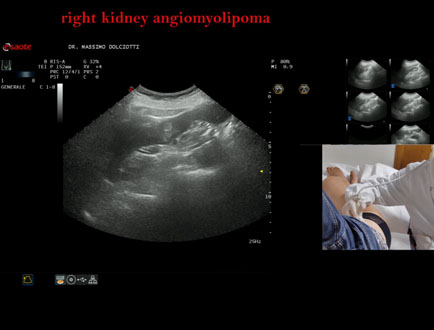

Data inserimento: 28/06/2023

Ecografia del: 26/06/2023

Strumento: Esaote MyLab Eight

Sonda: Convex Multifrequenza 1-8 MHz

Età Paziente: F 43 anni

Motivazione dell'esame: follow up per angiomiolipoma renale.

Commento all'esame: le immagini ed il video documentano la presenza di immagine iperecogena, in sede corticale del polo inferiore del rene destro, delle dimensioni di 10 mm, da ricondurre ad angiomiolipoma renale.

Conclusioni: angiomiolipoma renale destro (right kidney angiomyolipoma).

Presentazione: Dr. Massimo Dolciotti - Ancona

Elaborazione digitale: Andrea Dini - Ancona